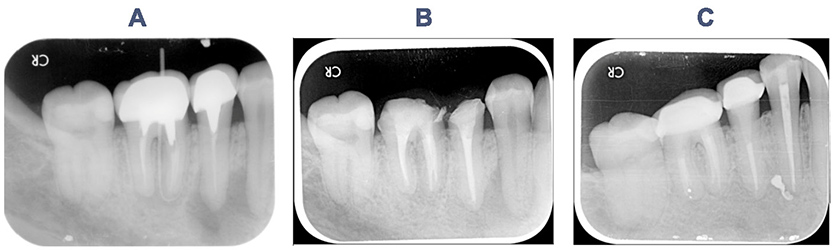

一名35歲女性,因右下後牙區牙齦出現膿包故前來就診。X光檢查可見右下第一小臼齒、第二小臼齒及第一大臼齒皆有根尖病灶黑影(圖A)。在拆除假牙、牙釘後,進行右下第二小臼齒及第一大臼齒非手術性重新根管治療(圖B)以及右下第一小臼齒根管治療。後續追蹤可見膿包及X光病灶皆已癒合(圖C)。